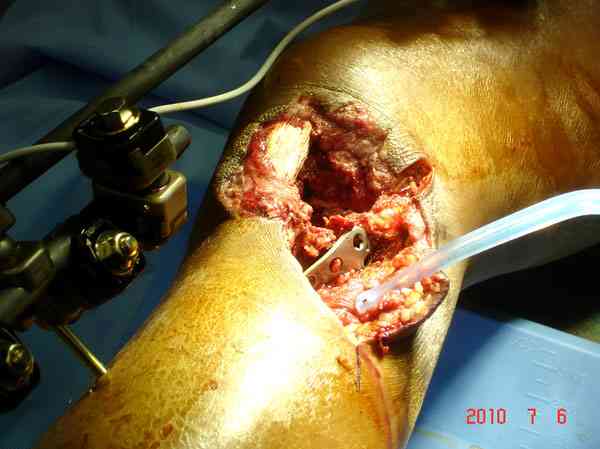

Имя     : 22 GSW size.jpg

Тип     : image/jpeg

Размер  : 75752 байтов

Описание: отсутствует

Url     : http://weborto.net:8080/pipermail/ortho/attachments/20100916/b1b36bf2/attachment-0008.jpg